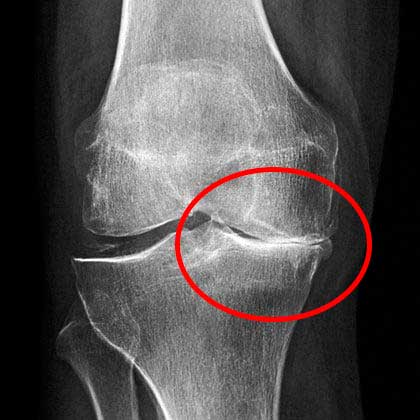

Di rumah sakit, dokter mengamati hasil rontgen saya cukup lama sebelum akhirnya memberi tahu bahwa saya tidak boleh lagi melakukan pekerjaan fisik berat atau mengangkat beban lebih dari 2 kilogram.

X-ray menunjukkan masalah serius dengan lutut saya

Berikut adalah kondisi lutut saya yang sehat saat ini